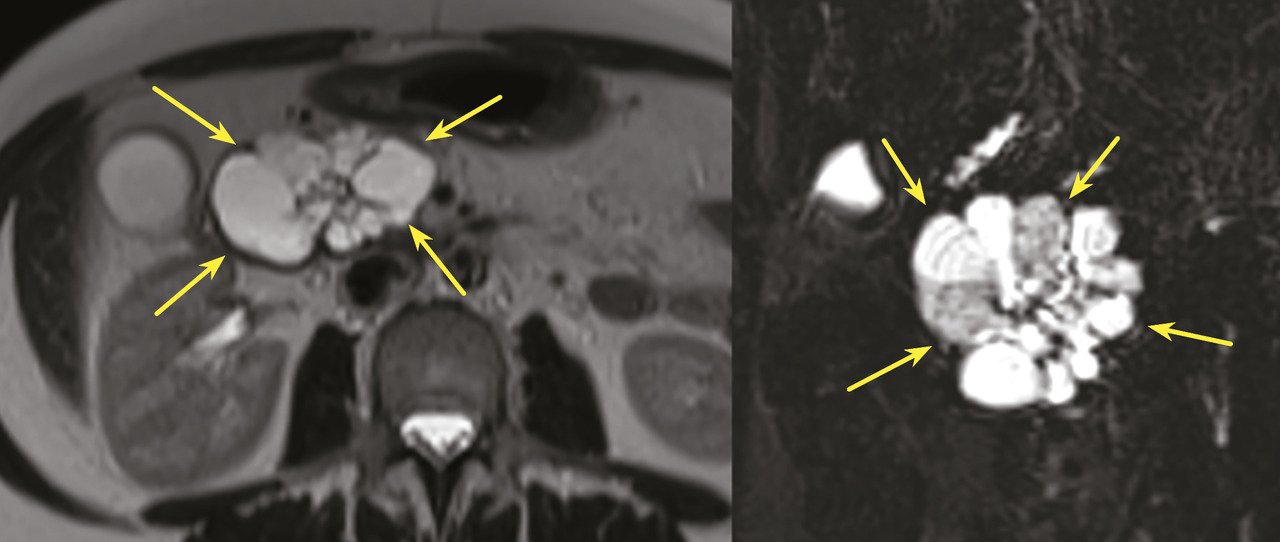

Les TIPMP sont des lésions canalaires intra-épithéliales développées aux dépens des canaux pancréatiques (principal ou/et secondaires) [fig. 1]. Elles prédominent au niveau de la tête et du crochet, mais peuvent concerner toute la glande. La composante kystique des TIPMP présente un épithélium de type mucineux avec production de mucus. Au cours du processus d’oncogenèse, des papilles commencent à se former, et différents phénotypes cellulaires distincts ont été décrits, corrélés à leur pronostic.

Les tumeurs kystiques mucineuses (TKM) sont des lésions précancéreuses bordées par un revêtement épithélial, sécrétant de la mucine. Il est caractéristique de trouver un stroma de type ovarien, positif en immunohistochimie à la progestérone. Le sex-ratio est fortement en faveur des femmes  : (20 femmes pour 1 homme). La découverte est principalement fortuite ou plus rarement sur pancréatite aiguë. Il s’agit d’une lésion unique, macrokystique, sans communication avec les canaux pancréatiques. Elle se situe quasi exclusivement au niveau de la face postérieure du corps et de la queue du pancréas (fig. 3). La lésion est uni- ou multiloculaire, limitée, hypodense, avec rehaussement de la paroi. Il existe de possibles nodules muraux, calcifications périphériques ou cloisons internes.

Toujours parmi les LKP rares à potentiel malin, on compte les tumeurs neuro-endocrines (TNE) kystiques (20 % des TNE pancréatiques) [fig. 5]. De découverte fortuite et non fonctionnelles, les TNE kystiques sont uniques, uniloculaires, bien différenciées, de bas grade, c’est-à-dire avec un indicateur de prolifération Ki67 < 3 %, et la présence d’une masse hypervasculaire (nodule) au niveau de la paroi. La partie charnue tissulaire peut être de petite taille.